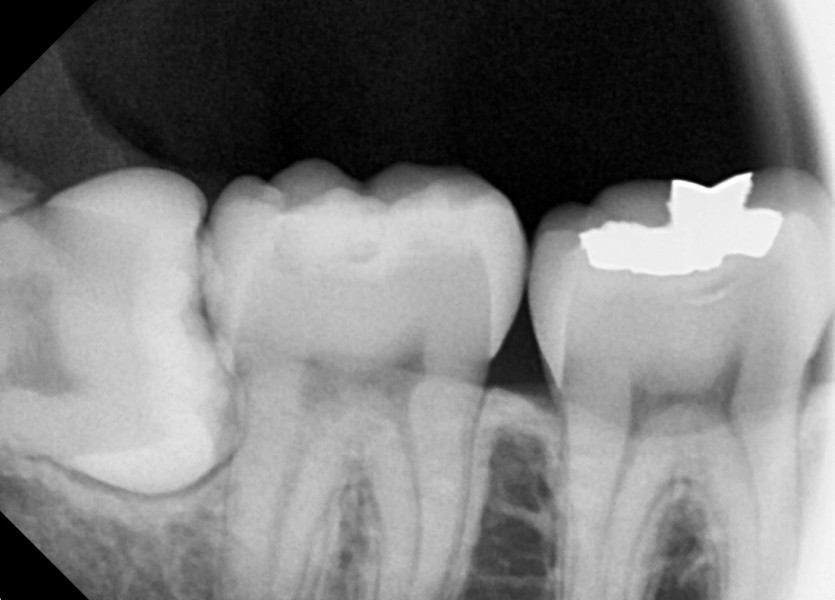

#38,48 사랑니 발치

구강 외과 전문의가 당일 발치했습니다.